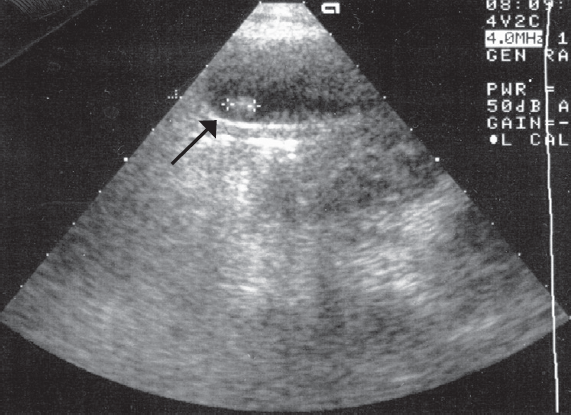

Research result. All patients with cholelithiasis identified different ways deformation in the area of gallbladder duct. One of the major causes of cholelithiasis in children are changes in the gallbladder duct. No patient has ever been found in concretions extrahepatic biliary passages. In patients with chronic stone-free cholecystitis pathology in the area of bladder flow was not found.